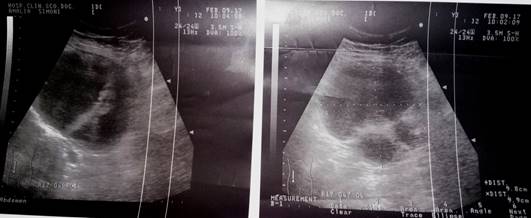

Estudios imagenológicos: se realizan tres USD de abdomen inferior donde siempre aparece una tumoración de aspecto quística entre siete y 12 cm, con celularidad y la pared es gruesa (Figura 1).

Resto del examen fue normal y en los estudios analíticos solo discreta elevación de la eritrosedimentación en 30 (mm/h). El dolor que había disminuido aparece de nuevo, intenso y se decide tratamiento quirúrgico urgente por TQO. Laparotomía media baja que confirma el diagnóstico; el quiste necrosado, de 15 cm se extirpa (Figura 2).